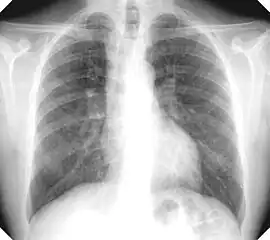

Complicated silicosis -

- Complicated silicosis

- Silicosis can become "complicated" by the development of severe scarring (progressive massive fibrosis, or also known as conglomerate silicosis), where the small nodules gradually become confluent, reaching a size of 1 cm or greater. PMF is associated with more severe symptoms and respiratory impairment than simple disease. Silicosis can also be complicated by other lung disease, such as tuberculosis, non-tuberculous mycobacterial infection, and fungal infection, certain autoimmune diseases, and lung cancer. Complicated silicosis is more common with accelerated silicosis than with the chronic variety.